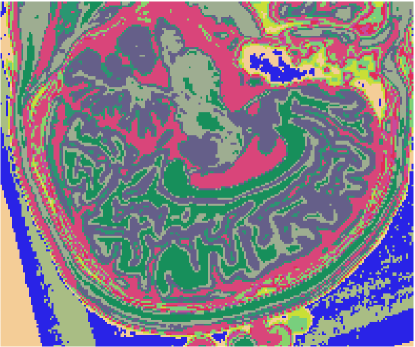

As figuras 2 (banda 0), 3 (banda 1) e 4 (banda 2) mostram a fatia 97 de um volume de imagens sagitais com 181 fatias e 0% de ruído, ponderadas em PD (densidade de próton), T1subscript𝑇1T_{1} e T2subscript𝑇2T_{2}, enquanto a figura 5 ilustra a composição colorida R0-G1-B2 da mesma fatia. Pode-se notar no topo do crânio, na parte inferior das imagens, a presença de artefatos, que podem ser resultantes de erros no simulador, mas que não são prejudiciais à análise, uma vez que, neste trabalho, não é dada ênfase à análise anatômica.

Refer to caption

Figura 5: Composição colorida R0-G1-B2 das imagens da fatia 97 ponderadas em PD, T1subscript𝑇1T_{1} e T2subscript𝑇2T_{2}

3.1 Classificadores Dialéticos Objetivos

A figura 6 mostra os resultados de classificação, enquanto a figura 7 exibe os resultados de quantização para a imagem sem ruído da fatia 97, figura 5, usando os métodos KO, CM, KM, ODC-PME e ODC-CAN. Esses resultados ilustram qualitativamente as diferenças entre os métodos de classificação e quantização, dado que a fatia 97 possui todas as 13 classes presentes na análise [51].

Figura 6: Composição colorida R0-G1-B2 das imagens da fatia 97 ponderadas em PD, T1subscript𝑇1T_{1} e T2subscript𝑇2T_{2} (a) e resultados de classificação usando os métodos KO (b), CM (c), KM (d), ODC-PME (e) e ODC-CAN (f)